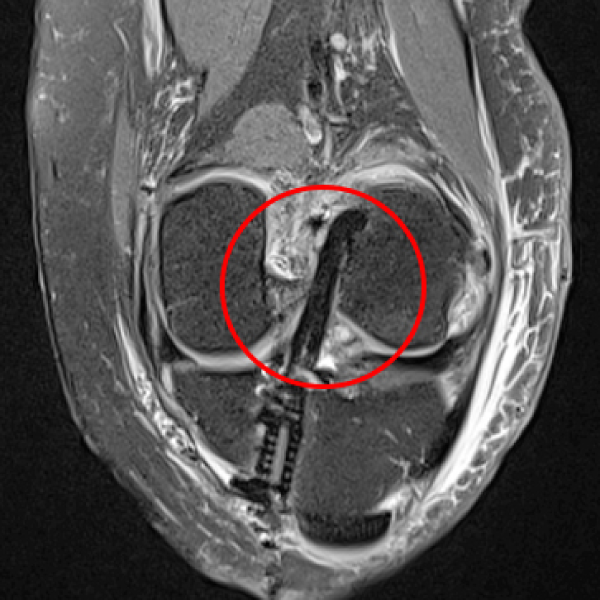

십자인대를 재건한 모습

2020.09.10